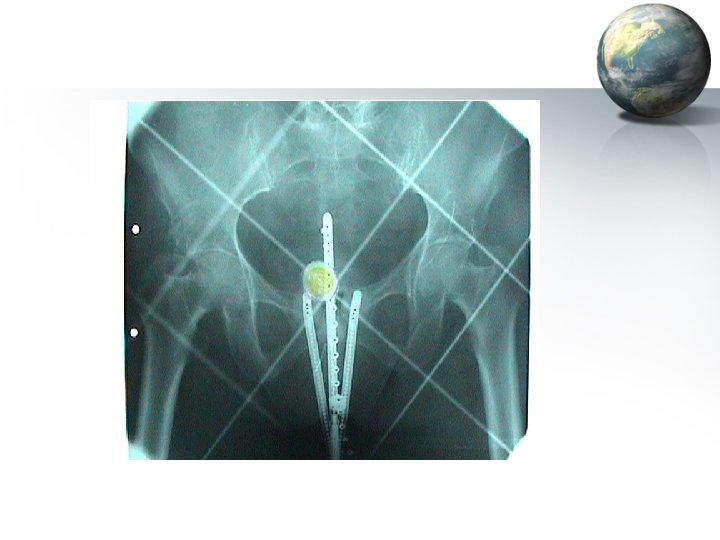

Brachytherapy • Radiation sources placed adjacent to the tumor by means of intra-uterine tandems and vaginal colpostats • Inverse square law : The dose of radiation at any given point is inversely proportional to the square of the distance from the source of the radiation The dose decreases rapidly as the distance from the applicator increases • Personnel protected by afterloading techniques • Brachytherapy helps in achieving central control of the tumor

Brachytherapy • Point A – It is a paracervical area located 2 cm lateral to the cervical canal and 2 cm above the external os – It corresponds to the crossing of the ureters under the uterine artery – Adequate summated dose to point A to achieve central control of the tumor is ~ 7500 – 8000 c. Gy • Point B – It is located 3 cm lateral to point A on the same horizontal plane – It corresponds to the site of the Obturator lymph nodes on the lateral pelvic wall – The prescribed dose to point B is 4500 – 6000 c. Gy depending upon the bulk of parametrial and side wall disease

Techniques of Brachytherapy • Low dose radiation (LDR) – Paris technique • One application : 120 hrs – Manchester technique • Two applications : 72 hrs each repeated after 7 days – Stockholm technique • Three applications : 24 hrs each at weekly intervals • High dose radiation (HDR) – Five fractions of 700 c. Gy each to Point A daily

Teletherapy • Radiation is directed towards tumor tissue from external sources like Cobalt 60, Caesium 137 or Linear accelerators • Usual dosage is 900 c. Gy / week in 5 fractions of 180 c. Gy each, given with or without central shielding • Teletherapy is usually given by parallel opposing fields or multiple external fields to decrease damage to normal tissues